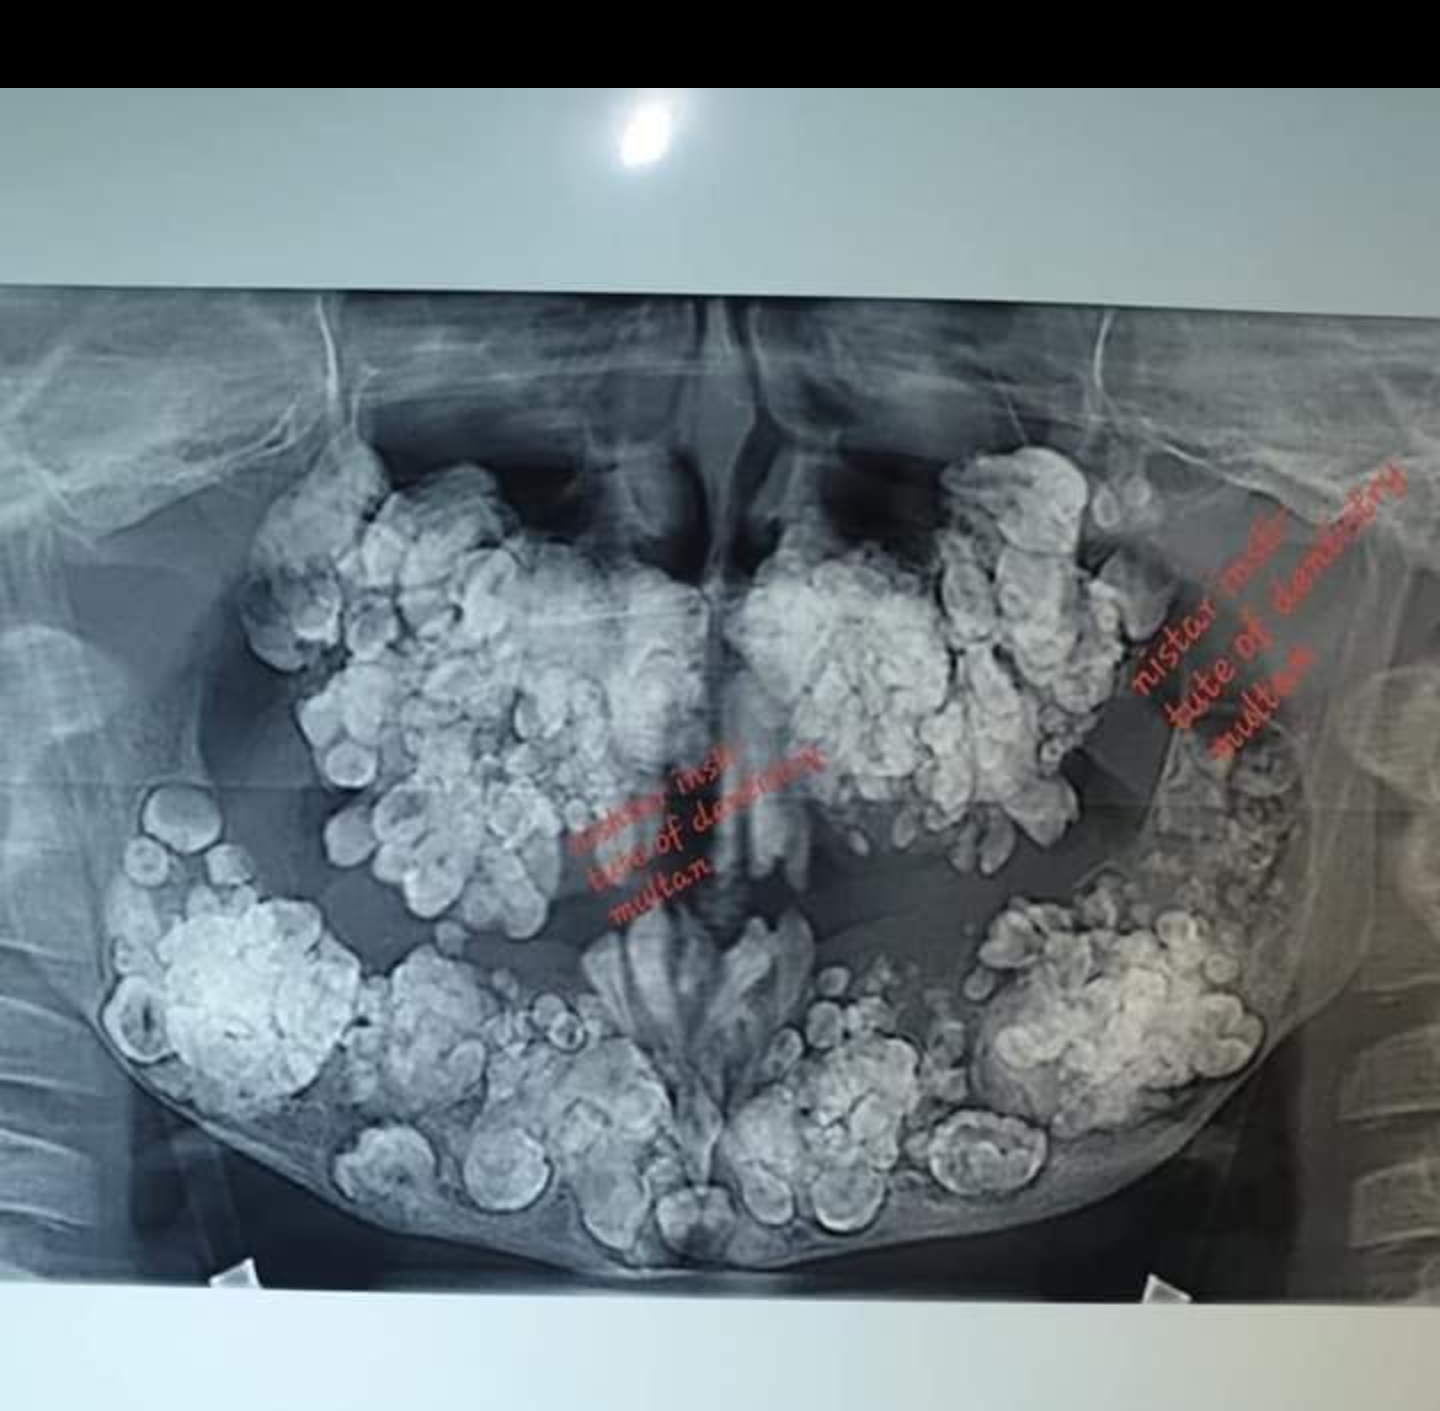

Hyperdontia is the condition in which a person is having extra number of teeth (32) , or known as supernumerary dentition .

A patient with hyperdontia is treated in Multan Nishtar Dental Hospital .